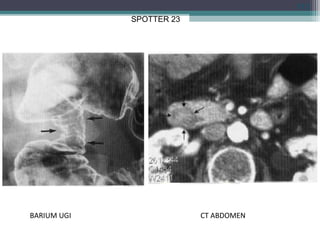

SPOTTER 23

• ANNULAR PANCREAS : NARROWING D2 &

CT SHOW GLAND ENCIRCLING D2.